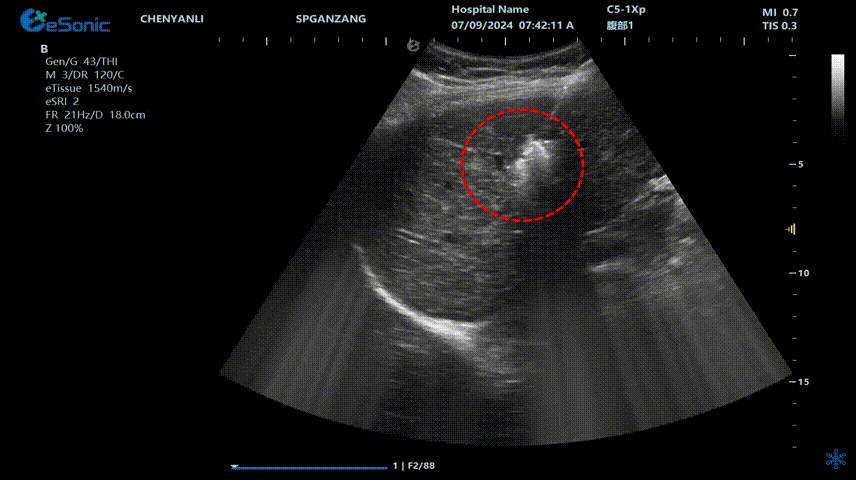

肝癌射频消融动态视频

红圈为病灶位置

肝癌射频消融:全麻下彩超探头引导射频针分别植入肝右叶两个稍高回声结节,固定消融,至结节全部为强回声覆盖,覆盖良好,缓缓灼烧针道后退针。